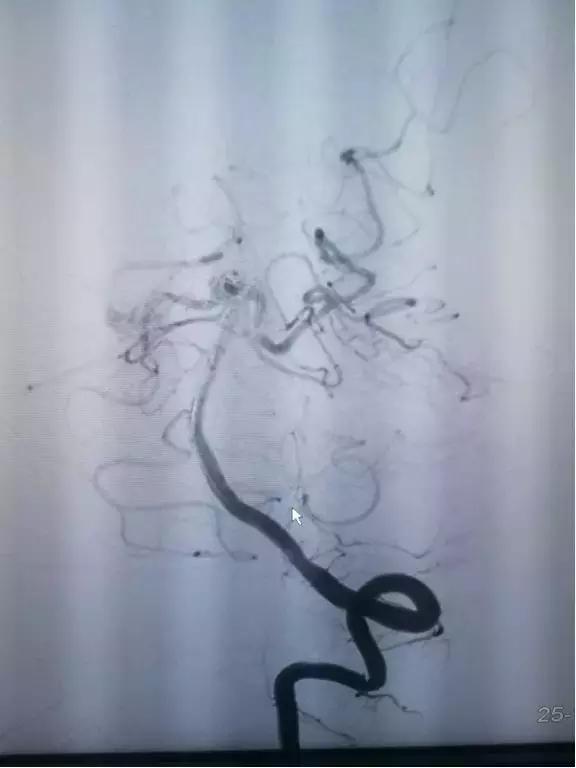

一个月前,患者因突发性头晕就诊我院,影像学检查显示:1、多发腔隙性脑梗塞,脑白质脱髓鞘改变,脑萎缩;2、鞍上池左旁异常信号,考虑动脉瘤可能(MR);3、基底动脉远端动脉瘤,4、颅内多发动脉硬化(MRA)门诊以“颅内动脉瘤”诊断收入院。入院后,张世荣主任团队考虑患者动脉瘤虽然未破裂,但是存在破裂的高危因素,建议做预防性手术,避免动脉瘤破裂引发的严重后果,并根据病情建议做介入栓塞治疗。

影像资料

从临床上来看,患者动脉瘤破裂的可能性大。再考虑到患者患有高血压且血压控制不理想,并且动脉瘤位于基底动脉远端,张世荣主任经过评估认为“虽然动脉瘤目前没有破裂,但是破裂风险较大,建议手术”,手术为介入栓塞术。

颅内动脉瘤介入栓塞术主要是在体外穿刺,将微导管直接插入到脑部瘤体内,再推入微弹簧圈,进行填塞,闭塞动脉瘤,消除动脉瘤破裂的可能。